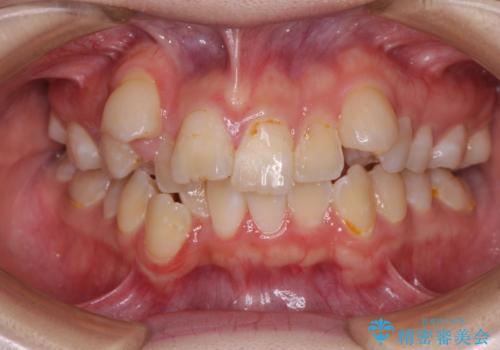

[マウスピース矯正] がたがたの歯並びをきれいにしたい

![[マウスピース矯正] がたがたの歯並びをきれいにしたいの症例 治療前](https://seimitsushinbi.jp/wp/wp-content/uploads/2025/06/0d238550c8a0fddc4de7b2c337c6c786-500x350.jpg?v=1750323380)